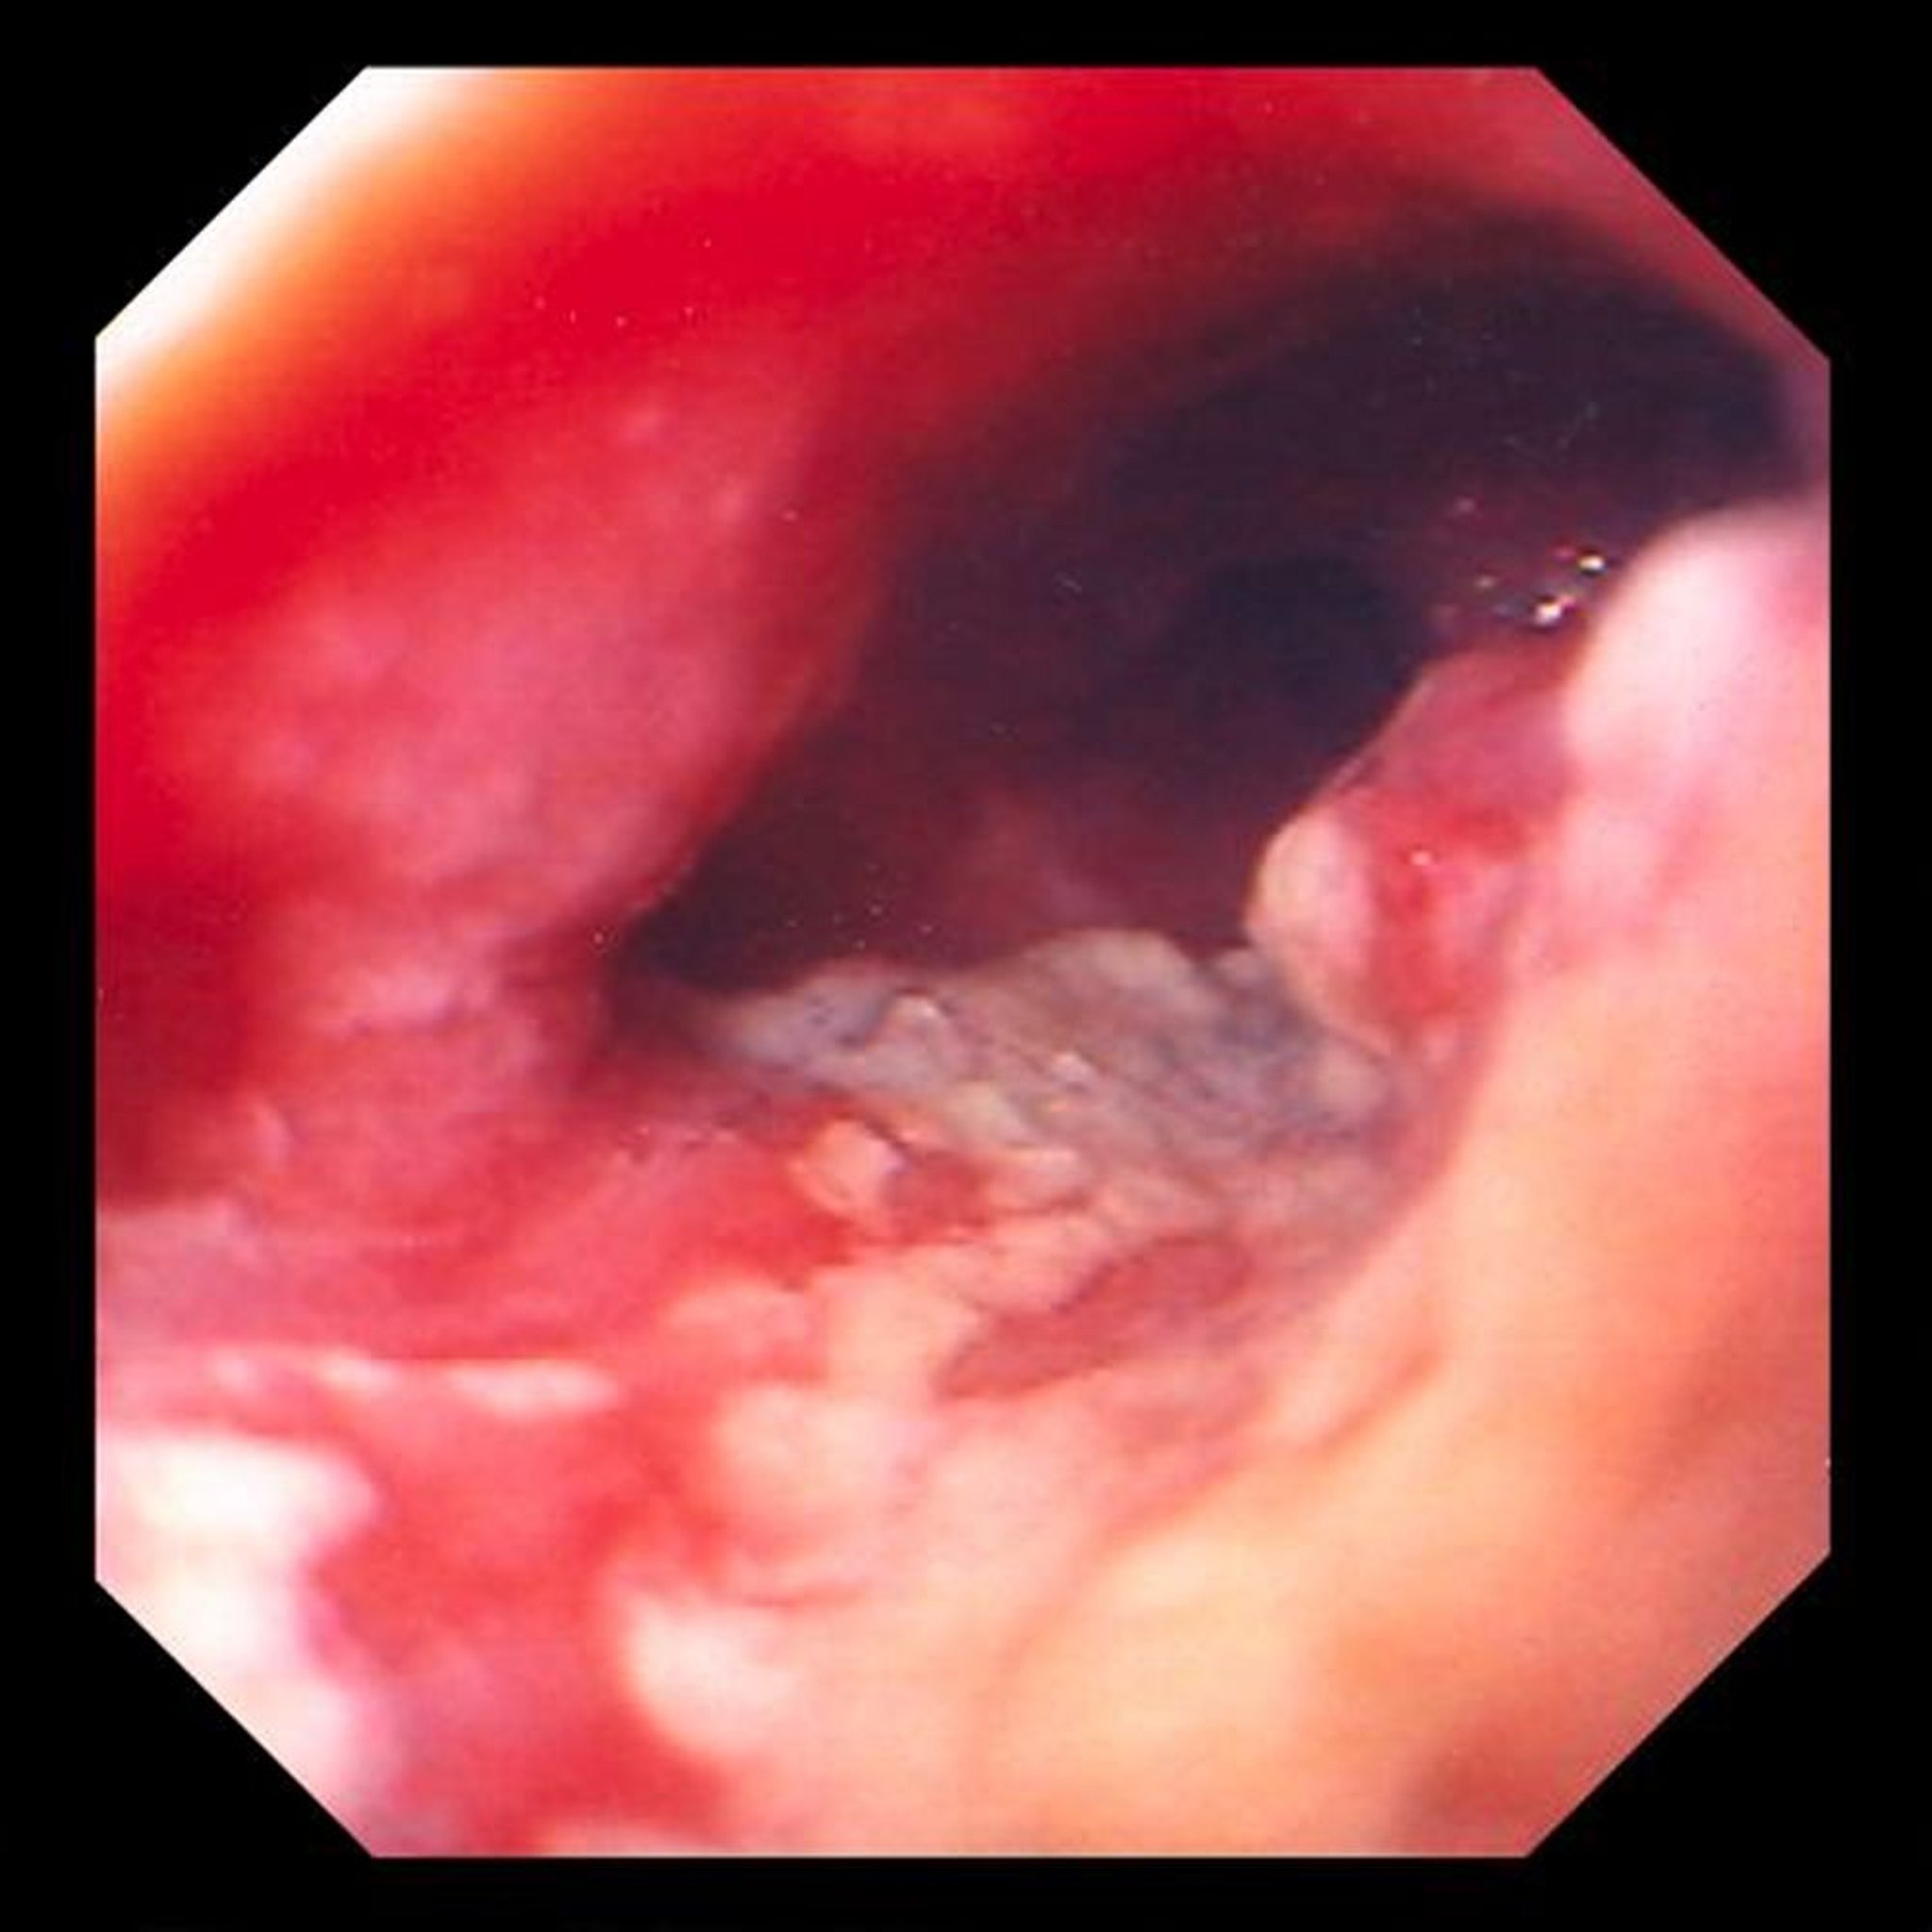

この画像には,下部食道の潰瘍を伴った狭窄性の腫瘍が写っており,円柱上皮の化生性変化(バレット食道)から発生した腺癌が強く示唆される。

Image provided by David M.Martin, MD.